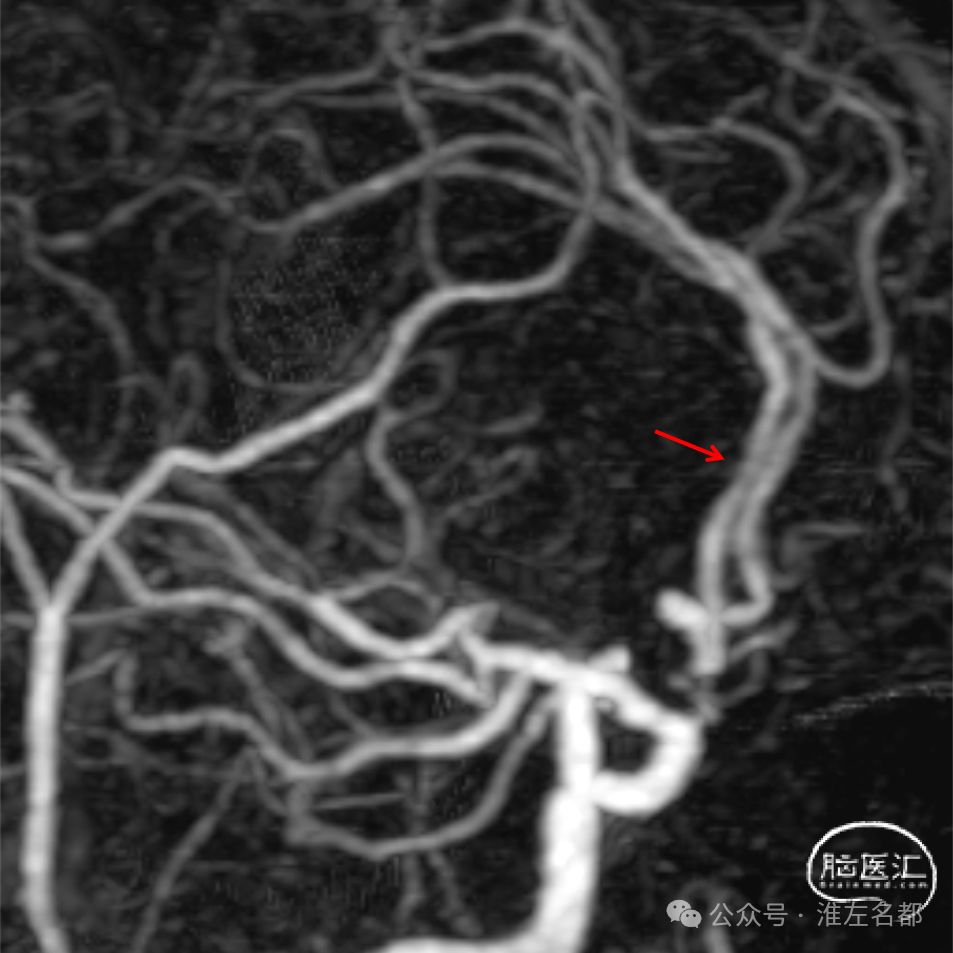

经微导管释放取栓支架(S AB 4*20mm)后造影,前向血流恢复,局部狭窄(红箭)。

回收取栓支架后造影:闭塞再通,右侧A2局部轻微狭窄,但A3-4交界处可见造影剂渗出,提示出血。